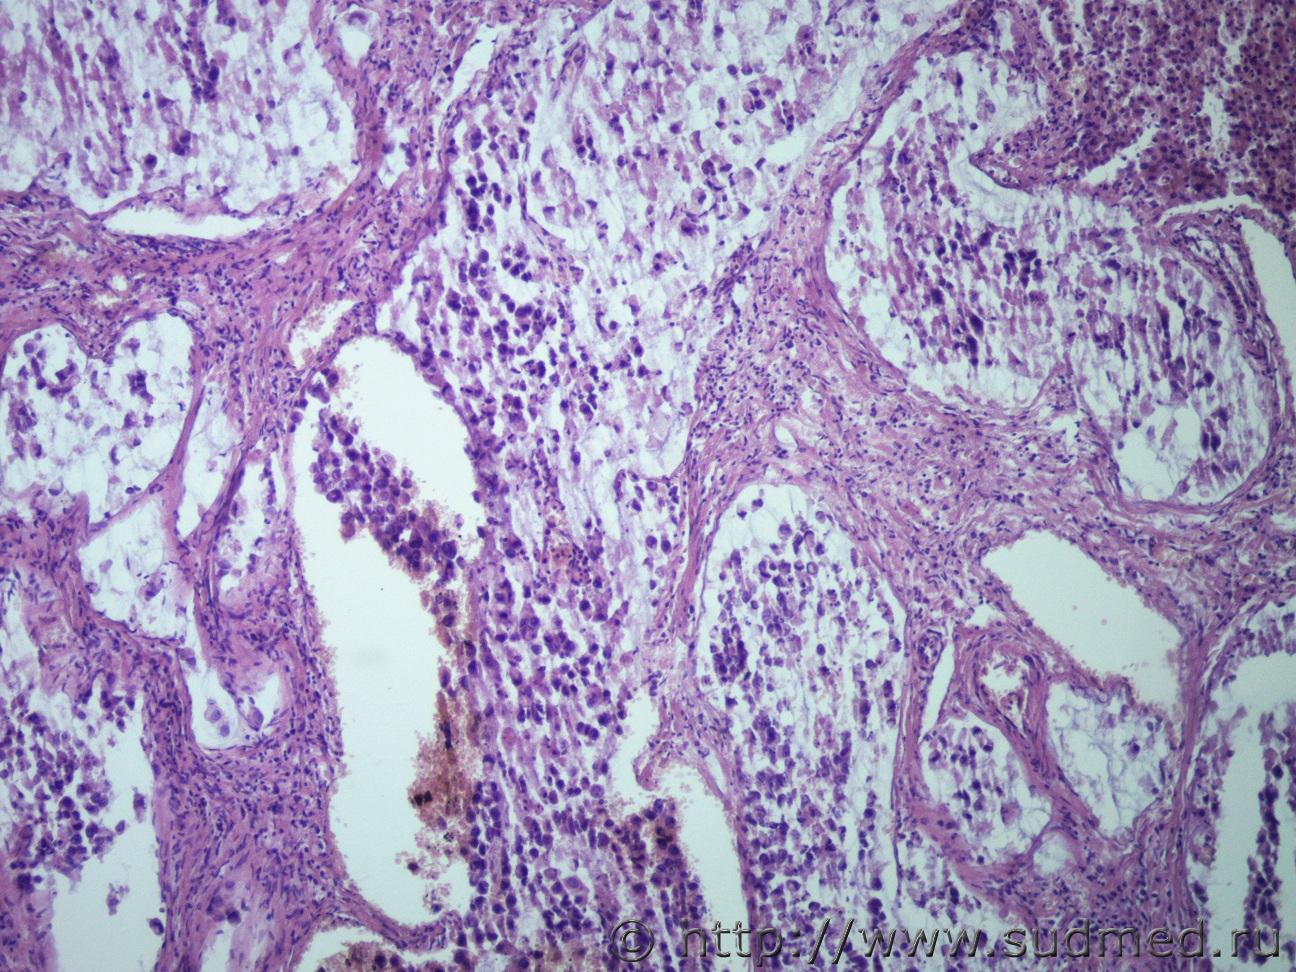

Метастазы в печени |

IVANNES Метастазы в печени 4.10.2019 - 09:53

Anton Вполне можно. ПКР. Особенно если добавить окраску ... 4.10.2019 - 13:08

IVANNES Вполне можно. ПКР. Особенно если добавить окраску ... 4.10.2019 - 14:03

Anton Что может быть скромнее альциановой синьки. Только... 4.10.2019 - 14:09

IVANNES Что может быть скромнее альциановой синьки. Только... 4.10.2019 - 14:30

Медик Перстневидноклеточный рак. 5.10.2019 - 18:50

доктор морфолог Коллоидный( слизистый рак) , либо аденкарцинома с ... 7.10.2019 - 13:15![]() ![]() |